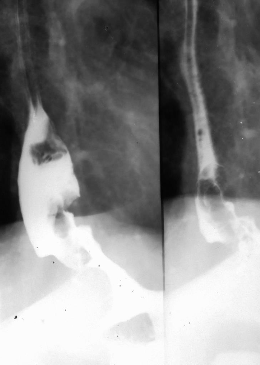

Diverticul Zenker